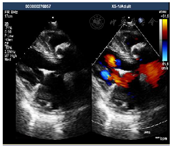

心脏超声:下腔静脉-右房-三尖瓣-肺动脉位人工带瓣管道依序连接,肺动脉人工管道内血流速度约2.3 m/s,压差约21 mmHg,下腔静脉内径约22 mm,略呈椭圆形,随呼吸运动变化幅度减低(图4)。

入院后,完善各项术前检查,包括心脏超声(图2),心脏及大血管CT(图3),调整患者营养状况,进行呼吸功能训练并多次进行多学科团队讨论。最后明确术前诊断:先天性心脏病:矫正型大动脉转位,室间隔缺损,肺动脉及其瓣下狭窄,二尖瓣中量返流,体肺侧支循环,间断加速性室性自主心律,室性早搏,房性早搏。